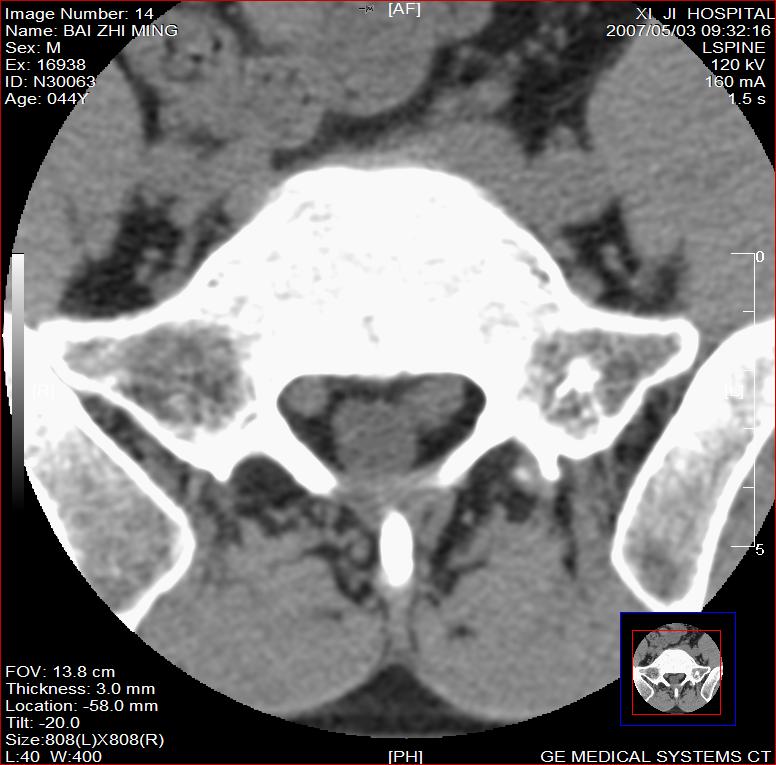

标题: CT8228:男,44岁,腰痛3月,加重3天,这是正常的吗?

男,44岁,腰痛3月,加重3天。

同意2楼,左侧神经根增粗,欠规整,神经根炎或神经源性肿瘤可能,建议mri检查。

左侧神经根增大.并硬脊膜囊受压(1,神经根炎2神经根肿瘤)

左侧神经根增粗,欠规整,神经根炎或神经源性肿瘤可能,建议mri检查